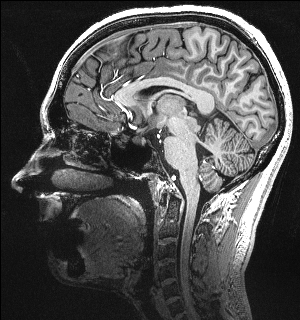

High-Resolution Structural Imaging

In addition to the modalities above, we also acquire high-resolution T1 and T2w modalities including MPRAGE, MP2RAGE, SPACE, TSE, FLAIR and MT images for brain morphometrics, hippocampal subfields, and locus coeruleus/circle of willis imaging.

Imaging parameters

- MPRAGE: 0.75 mm isotropic resolution, acquisition time = 6 min

- MP2RAGE: 0.55 mm isotropic resolution, acquisition time = 13 min

- SPACE: 0.6 mm isotropic resolution, acquisition time = 10 min

- TSE: 0.375x0.375x1.5 mm3 resolution, acquisition time = 4 min for hippocampus segmentation, 8 min for whole brain

- FLAIR: 0.75x0.75x1.5 mm3 resolution, acquisition time =11.5 min

- MT: 0.4×0.4×0.5 mm3 resolution, acquisition time = 4:38 min